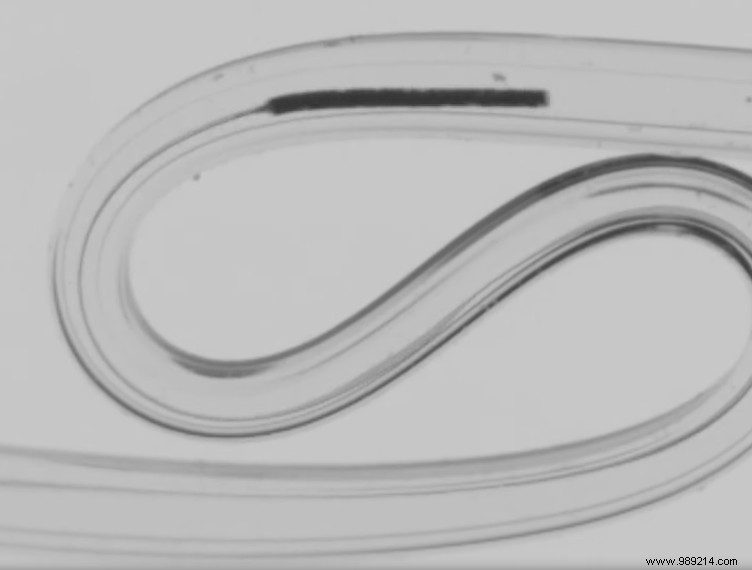

EPFL's team created a microscopic device, demonstrated in the video at the article's end, capable of entering arterioles or even capillaries—the body's finest blood vessels. Insertion is swift and straightforward.

This device complements traditional catheters with its ultra-flexible, biocompatible polymer body and tip—likened to a fishing line and hook. Clinicians hold the proximal end, allowing blood flow to propel it through peripheral vessels. Gentle magnetic twists enable path selection without stressing vessel walls, as no mechanical force is applied.